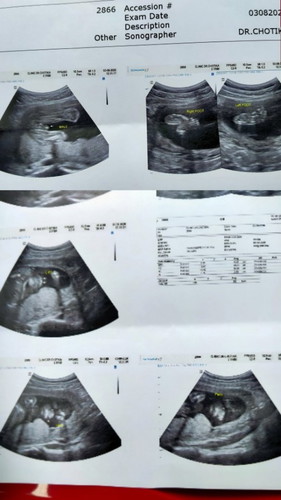

ชายหรือหญิง

แบบนี้ชายใช่มั้ยค่ะ

* ถ้าระบุว่าMALEก็ชายค่ะแม่

ผ.ช ค่ะ มีจู๋